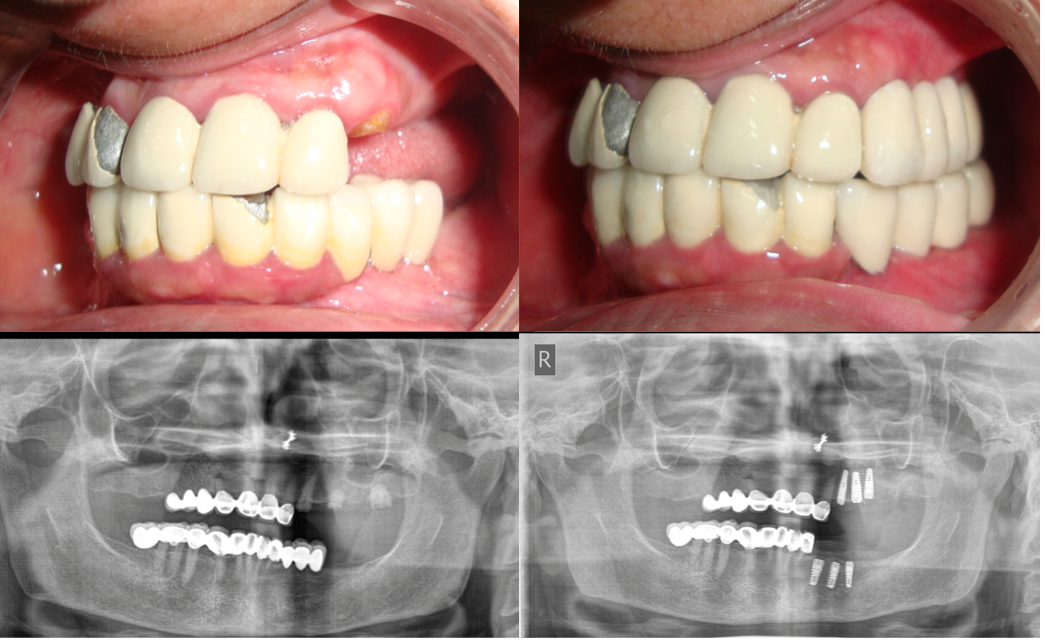

Multiple Teeth Replacement

Card image